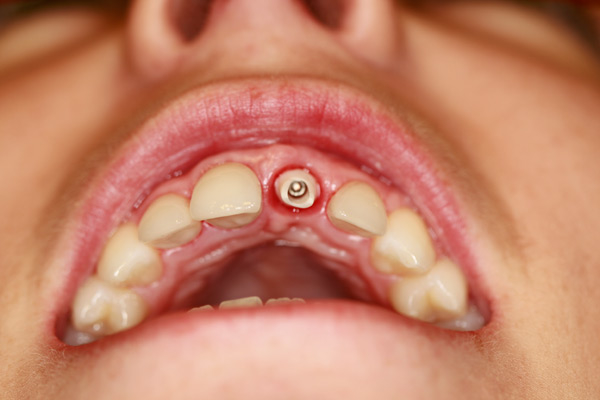

Problem: This young patient lost her front tooth. She also had a dark tooth that was treated with a root canal.

Plan: Our plan… placed an implant then molded the tissue for a few months to get the best appearance. A zirconium abutment was used to restore the tooth and veneers on the other three front teeth.

Creating beautiful smiles.